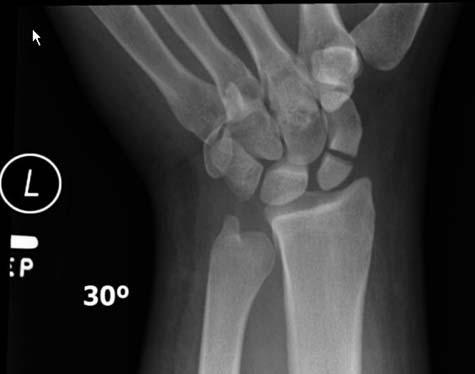

Nineteen of the 36 patients were found to have a radiographically apparent injury. The most common injuries involved the upper extremities, particularly the wrist. There were six cases of distal radial fractures, or fracture of the forearm bone close to the wrist, making it the most common injury in the study group. Soft tissue injuries of the head, face, wrist and ankle, were present in five cases.